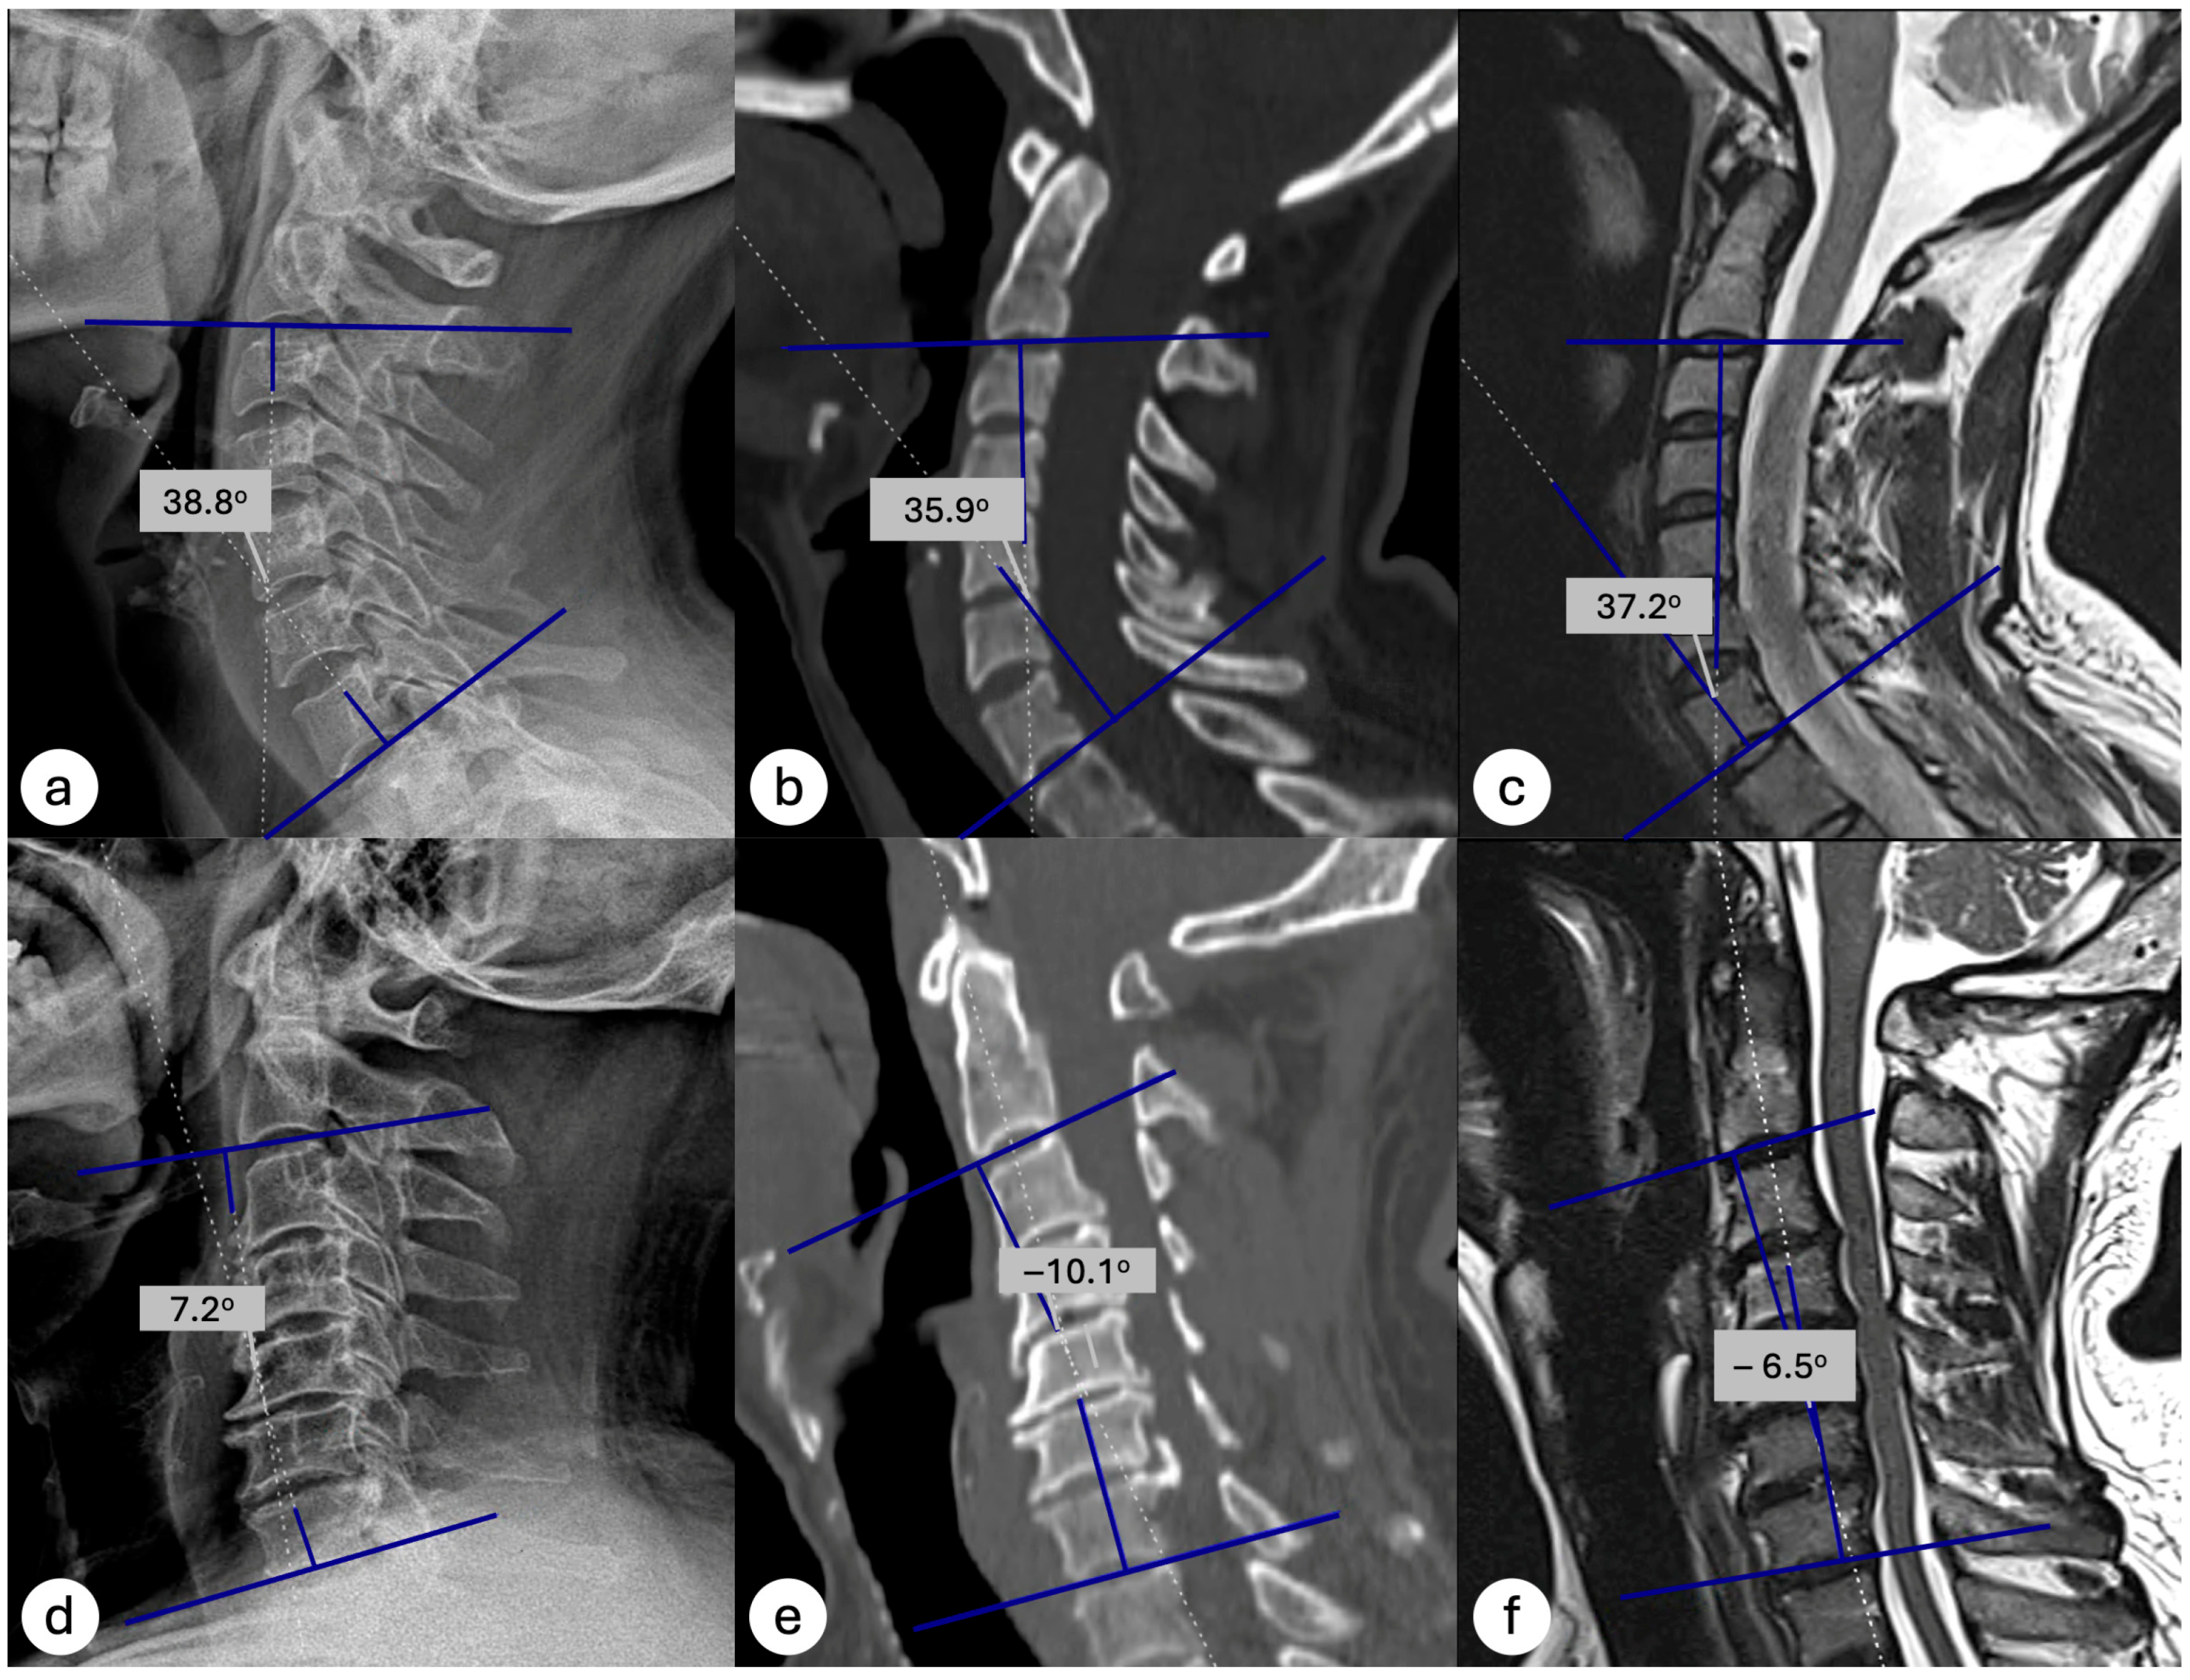

MRI showed comparable diagnostic values, with a sensitivity of 88%, specificity of 85%, PPV of 52%, and NPV of 98% when the standard threshold (0°) was used. Notably, when applying a threshold of >1.20°, MRI achieved a 100% NPV, meaning that no patient with a Cobb angle greater than 1.20° on MRI was found to have kyphosis on standing radiographs (Table 4). Demonstrative case examples are shown in Figure 3. These results suggest that both modalities are highly reliable in excluding kyphotic alignment, but confirmation with upright radiographs is required when kyphosis is suggested on supine imaging.

Figure 3. Demonstrative cases of cervical lordosis measurement across imaging modalities. Top row (Case 1): Cobb angle measurements on standing lateral radiograph (a), supine CT (b), and supine MRI (c) demonstrate lordotic alignments of 38.8°, 35.9°, and 37.2°, respectively, classifying the case as non-kyphotic in each modality. Bottom row (Case 2): The patient’s supine CT (−10.1°) (d) reveals a non-kyphotic, lordotic curvature, illustrating how cervical lordosis can appear diminished or reversed on supine imaging but re-emerge under weight-bearing conditions (e) and supine MRI (−6.5°) (f) both show kyphotic alignment, whereas the standing lateral radiograph (7.2°).